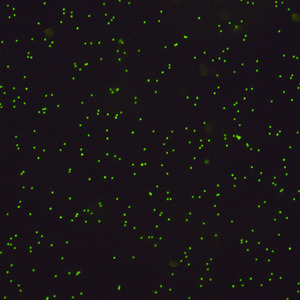

荧光成像(Fluorescence imaging):

荧光寿命显微成像(FLIM)已经广泛应用于生命科学研究领域,具有高灵敏和高特异性的特点。利用荧光现象的机理,在显微光路上使用特定的激发光源和相应的滤片,即荧光显微镜,实现对生物样品分子发光(荧光团)的观察,从而实现对生物样本的定性和定量分析。荧光显微镜的基本结构如图所示。

荧光显微技术在生物学和医疗领域中应用是最广泛也是最复杂的。针对不同样品和目标,需要考虑不同的荧光标记策略,一是荧光染料能标记的目标,二是荧光染料对应的激发特征,包括吸收光谱特征和发射光谱特征。